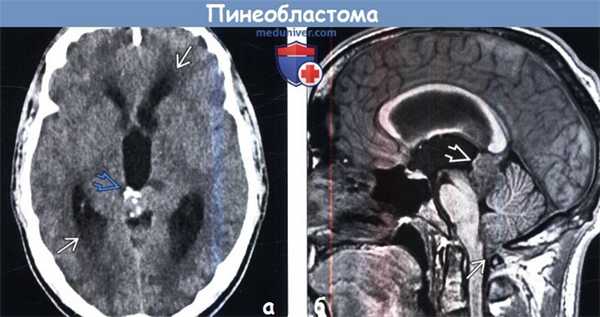

(а) Бесконтрастная КТ, аксиальный срез: определяется инфильтративное, умеренно гипер-денсное объемное образование с нечеткими границами, сконцентрированное вокруг пинеальной области. Обратите внимание на кальцификаты, расположенные в периферических отделах опухоли. При подробной оценке обнаруживается инвазия прилежащих тканей мозга. Определяется компрессия сильвиева водопровода, вызывающая развитие гидроцефалии.

(б) МРТ, ДВИ, аксиальный срез: определяется ограничение диффузии в области солидного объемного образования. Данная методика позволяет более четко визуализировать границы новообразования и инвазию прилежащей ткани мозга.

(а) Бесконтрастная КТ, аксиальный срез: у мужчины 23 лет, поступившего в приемное отделение с жалобами на сохраняющиеся в течение нескольких недель головных болей и с недавно появившимся затуманиванием зрения, в пинеальной области определяется кальцифицированное объемное образование.

Наблюдаются умеренная обструктивная гидроцефалия и «стуше-ванность» стенок увеличенных боковых желудочков.

(б) MPT, Т1-ВИ MPRAGE, сагиттальный срез: у того же пациента в пинеальной области определяется дольчатое объемное образование. III/боковые желудочки умеренно увеличены в размерах, наблюдается нисходящая дислокация миндалин мозжечка.